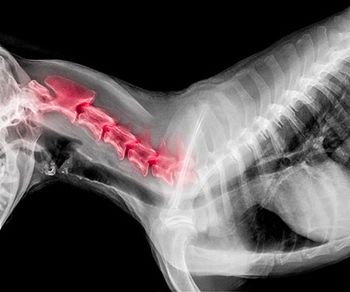

Intervertebral disk disease in dogs can be a devastating diagnosis, with treatment decisions often based both on the neurologic status of the patient and the economics of the owner.

Recommendations for medical management of IVDD have changed, and corticosteroids are once again in the spotlight.